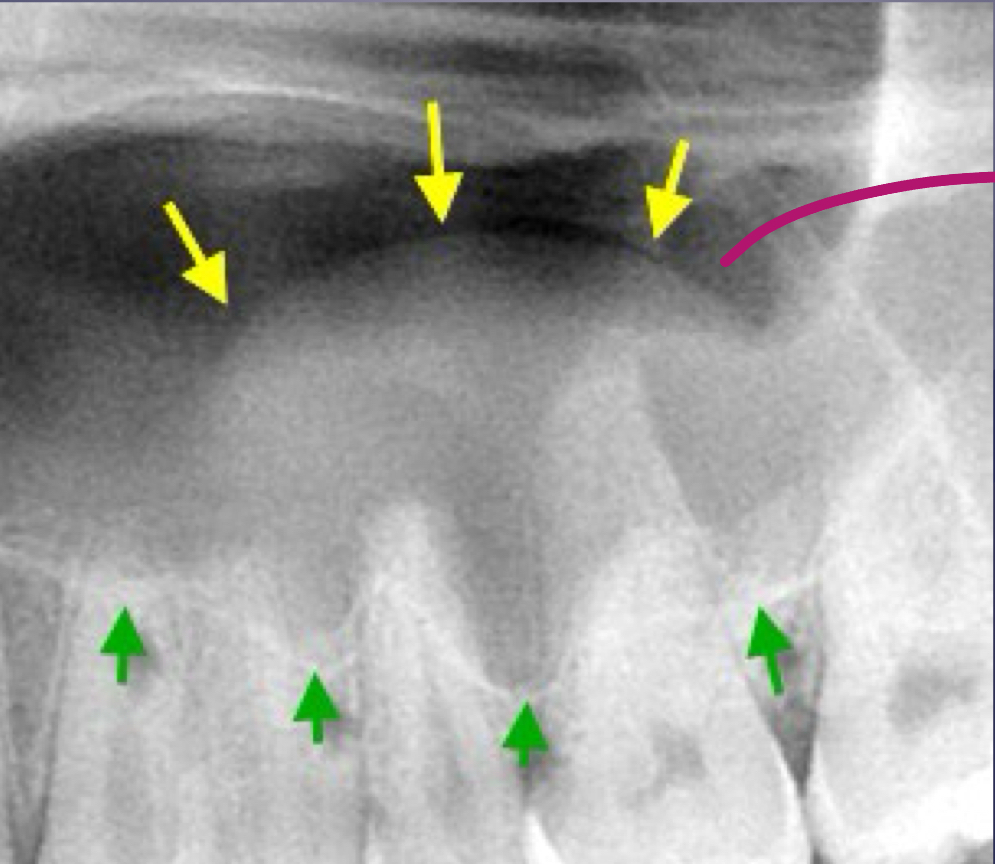

what are some effects of periapical inflammatory disease on surrounding structures?

bone deposition

alteration in trabecular bone pattern and marrow spaces

periosteal new bone formation

perforation of bone border

halo sign

elevation/displacement of floor f maxillary sinus

maxillary posterior teethÂ

periostitis/onion skin

periostitis, onion skin

periosteal bone formation in floor of maxillary sinus

periostitis and mucositisÂ

mucosal thickeningÂ

mixture of rarefying and sclerosing osteitis

no pathology, submandibular gland fossa